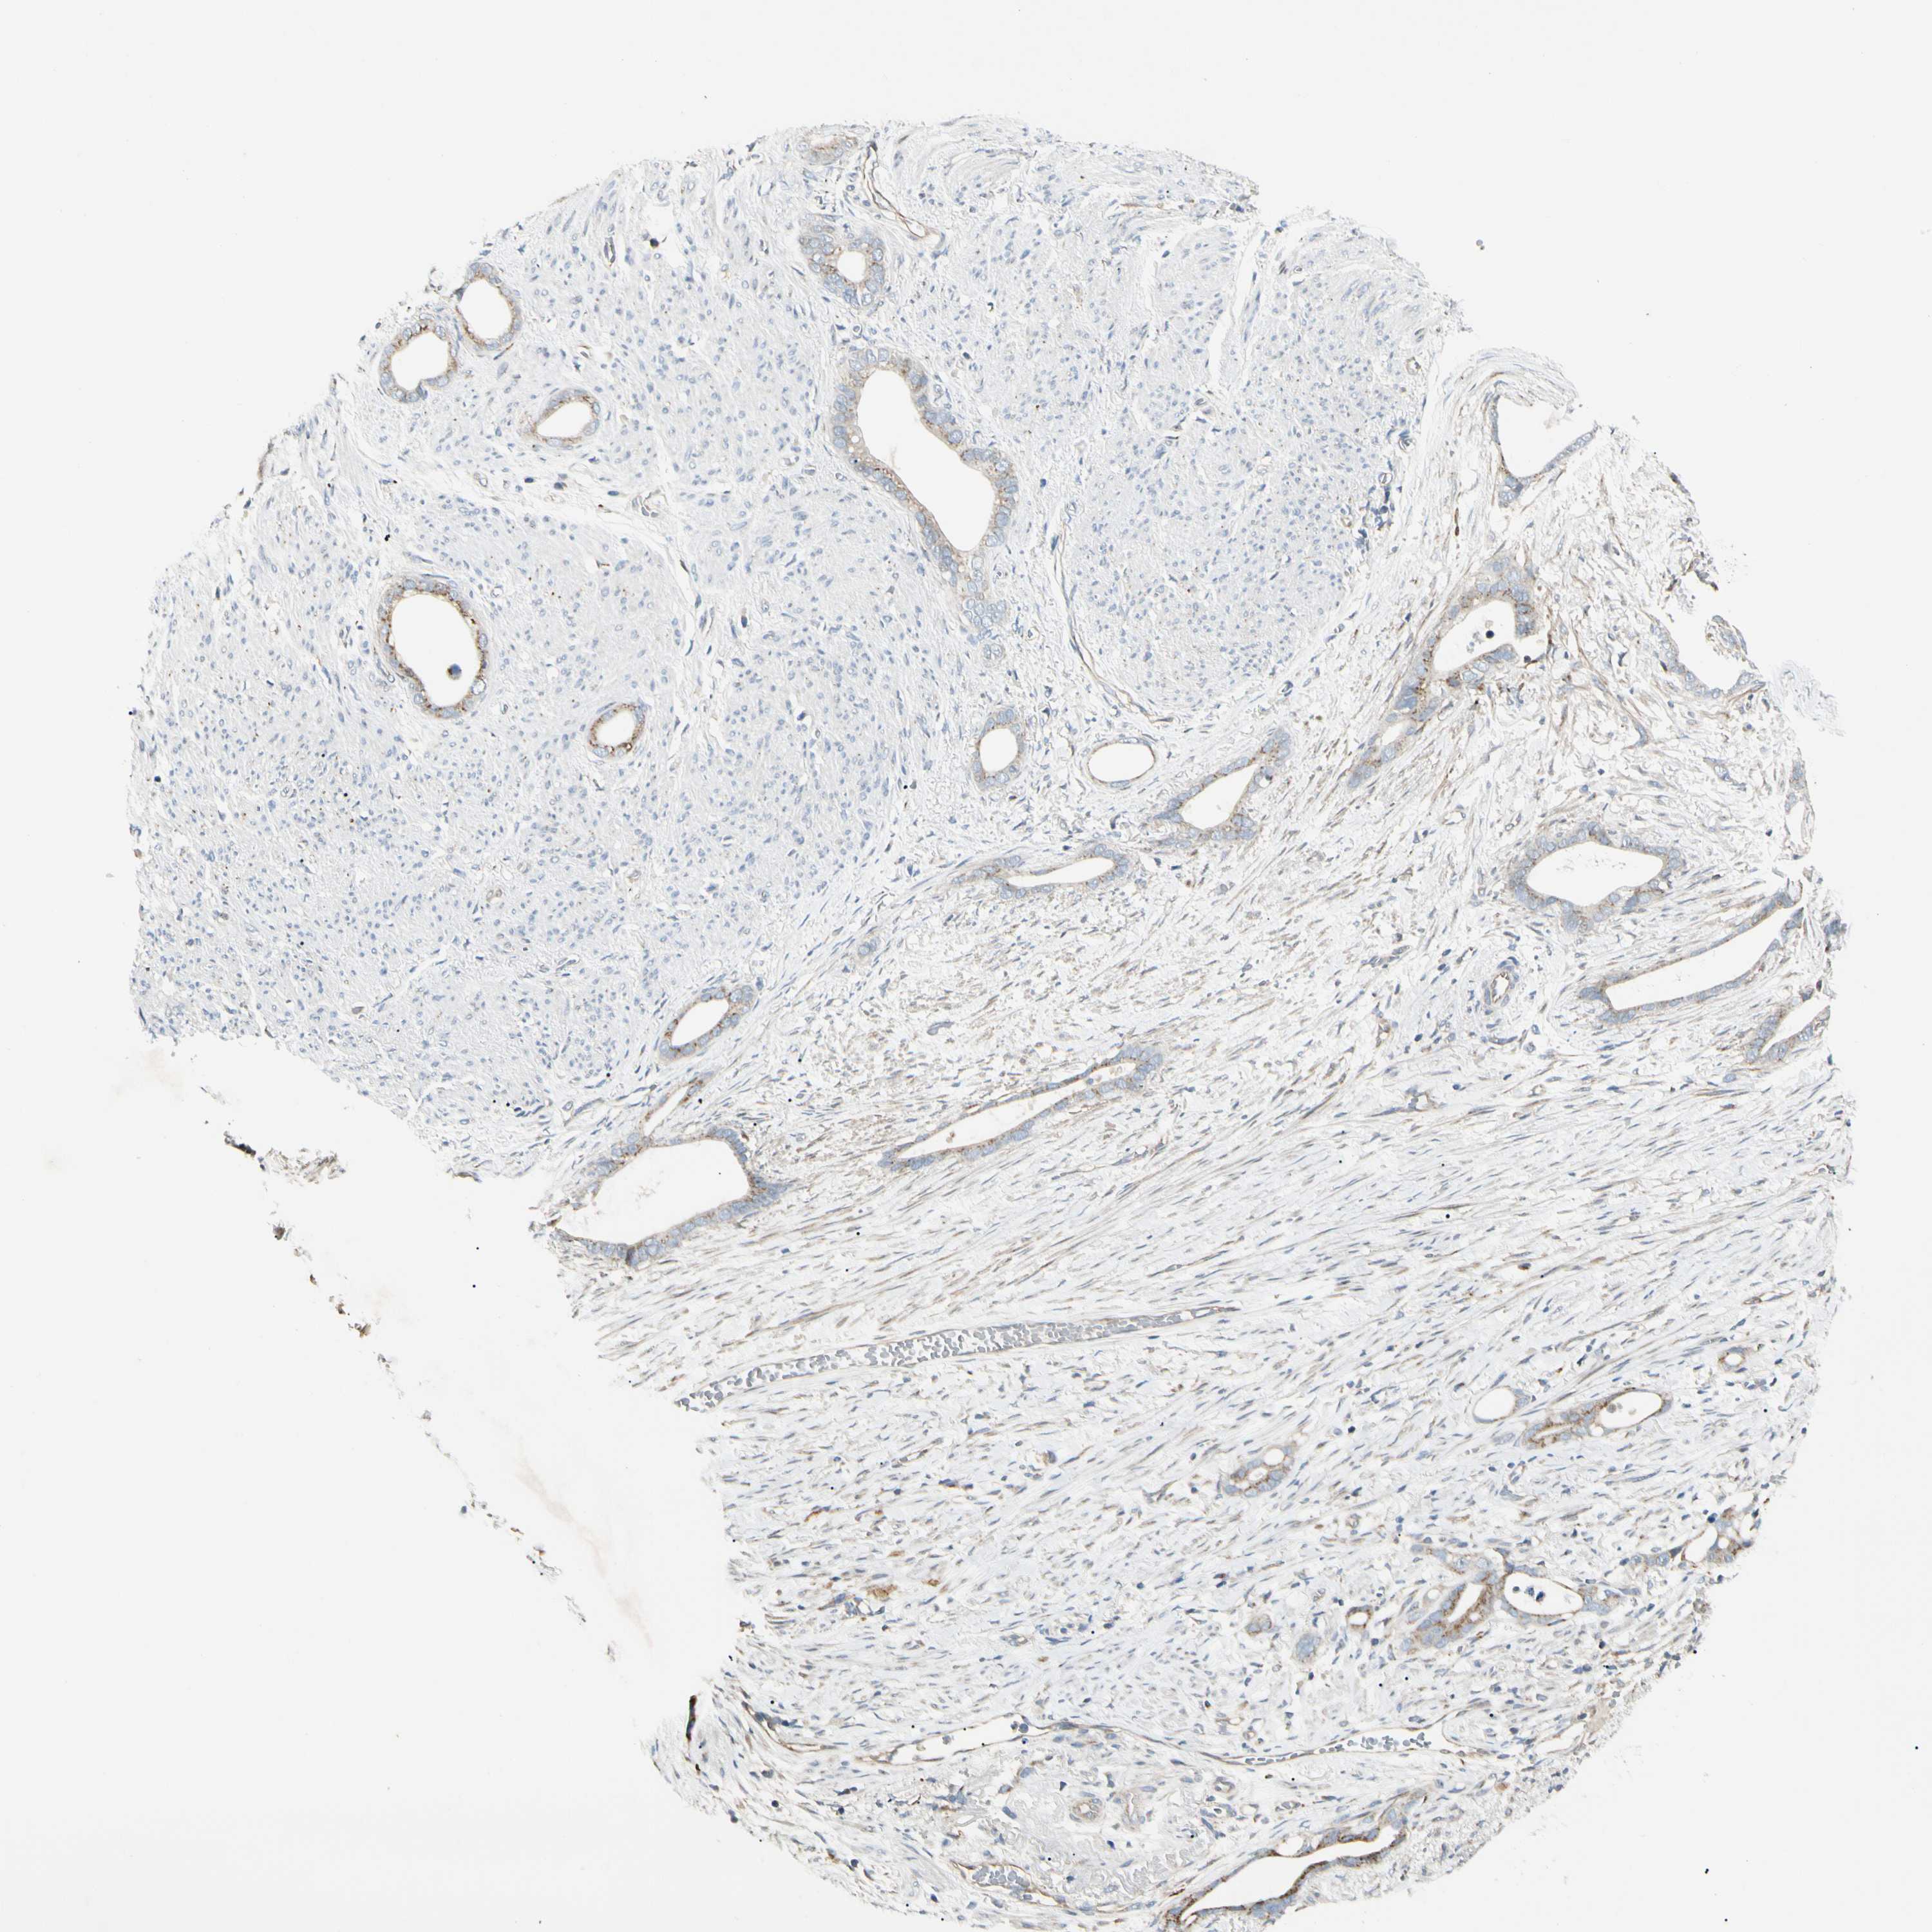

STOMACH CANCER - Protein expressioni

A mouse-over function shows sample information and annotation data. Click on an image to view it in a full screen mode. Samples can be filtered based on level of antibody staining by selecting one or several of the following categories: high, medium, low and not detected. The assay and annotation is described here.

Antibody stainingi

Antibody staining in the annotated cell types in the current human tissue is reported as not detected, low, medium, or high, based on conventional immunohistochemistry profiling in selected tissues. This score is based on the combination of the staining intensity and fraction of stained cells.

Each image is clickable and will lead to virtual microscopy that enables deeper exploration of all samples and also displays staining intensity scores, fraction scores and subcellular localization as well as patient and tissue information for each sample.

Antibody HPA007884

Staining

High

Medium

Low

Not detected

Intensity

Strong

Moderate

Weak

Negative

Quantity

>75%

75%-25%

<25%

None

Location

Nuclear

Cytoplasmic/membranous

Cytoplasmic/membranous,nuclear

Adenocarcinoma, NOS